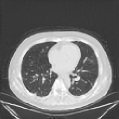

IV-F1 GeMix leads to more realistic images

One of our hypotheses is that GeMix is supposed to lead to more realistic images than traditional mixup or MMixup. Figure 2 illustrates a few examples produced by mixup (first column), MMixup (second column) and GeMix (third column). We observe that GeMix produces more anatomically coherent images, whereas the interpolation in pixel-space performed by mixup and MMixup leads to images that are not anatomically valid.